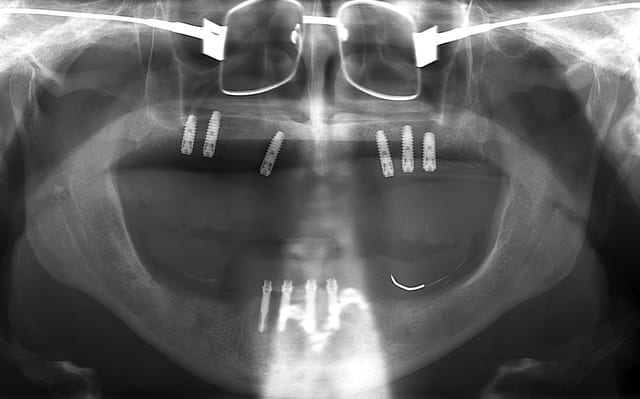

vis de cicatrisation sur une expansion réalisée en mars 09 à Sallanches implants en 13/14/15/18 pour une barre et PT.

Interessante car fracture de l'os vestibulaire y compris de la bosse canine, vitalos mais pas de vis d'ostéosynthese, et comme je sais que le doute est toujours present, ouverture large, avec décollement plus que necessaire pour controle.

sur l'implant en 14 une feuille d'os , en 13 un petit creux en mesio vestibulaire et 15 nickel.

il ne s'agit pas de montrer que cette technique est la seule, mais juste que dans ce cas tout va bien.

merci Thomas je suis bien rentré (croisé 6 paires de "jumelle" avec des habits bleus, mais à chaque fois coup de bol...)et je ne résiste pas au plaisir de passer le pano de notre ami.

Bien sur c'est du travail "d'amateurs", les axes sont nuls mais il semblerait que ton patient va l'avoir son amovo-inamovible!

y'en a même une sur l'OPT n°2 !!!